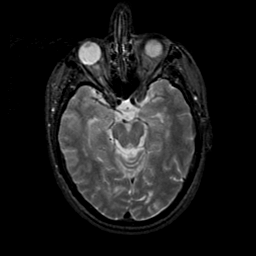

MR Study #23, January 26, 1992 -- Slice #19